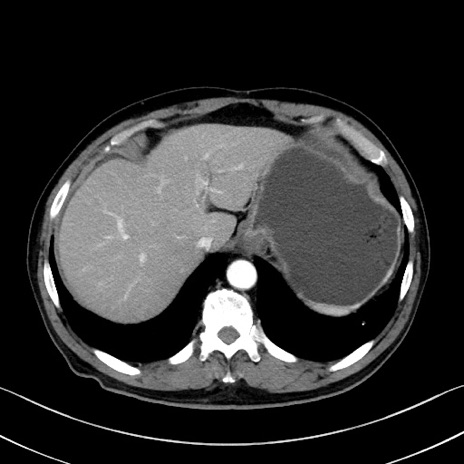

症例35(横断像)

【症例】70歳代 男性

【主訴】腹部膨満、嘔吐

【現病歴】昨日より腹部膨満感出現。本日増悪し、仙痛出現。嘔吐あり、受診。

【既往歴】糖尿病、胆摘後

【身体所見】BP 149/80mmHg、HR 74/min、BT 35.9℃、腹部:膨満、軟、圧痛なし。腸雑音減弱あり。上腹部正中切開瘢痕あり。

【データ】WBC 13500、CRP 1.72